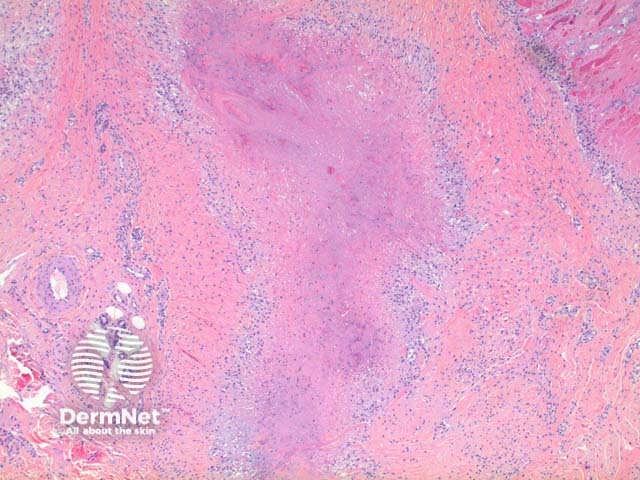

In a rheumatoid nodule, scanning power view reveals a granulomatous tissue reaction pattern (Figure 1). Well formed necrobiotic granulomas form within the dermis frequently with deep extension (Figure 2). There is a surrounding palisade of histiocytes and a mixed infiltrate of lymphocytes, plasma cells, multinucleated giant cells and occasional eosinophils (Figure 3).

Figure 1

Figure 2

Figure 3